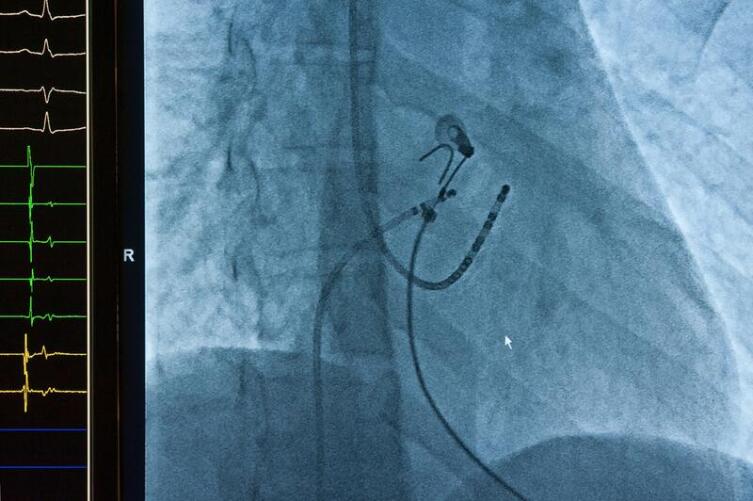

При пароксизмальной на фоне нормального ритма вдруг возникает сильное ускоренное и беспорядочное сердцебиение в сопровождении крайне неприятных физических и психических симптомов. Лекарственное лечение малоэффективно, зато дефибрилляция - воздействие довольно мощным электрическим импульсом - как правило успешно восстанавливает нормальный ритм.

Если врачи считают, что показана дефибрилляция (электроимпульсная терапия), отказываться ни в коем случае не следует.

Лаура Ли, фибрилляция предсердий/мерцательная аритмия никак не контролируется пейсмейкером.

Пейсмейкерами (искусственными водителями ритма/кардиостимуляторами)лечатся блокады- нарушения проведения импульсов в проводящей системе сердца и синдром слабости синусового узла- при котором сердце не способно само вырабатывать управляющие импульсы.

Существуют еще пейсмейкеры-дефибрилляторы.

Они отслеживают приступы фибрилляции (трепетания) не предсердий, а желудочков сердца, и довольно мощным электрическим импульсом обрывают его, восстанавливая нормальные сокращения и предотвращая внезапную смерть, например в случае приступа Морганьи-Эдемс-Стокса.